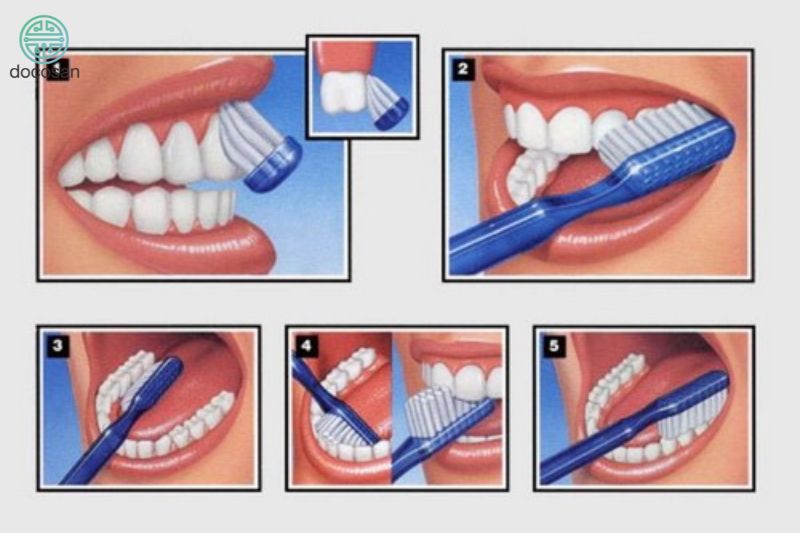

Chăm sóc vệ sinh răng miệng sạch sẽ: có một số kỹ thuật có thể được sử dụng để làm sạch răng một cách sạch sâu mà không cần phẫu thuật. Tất cả chúng đều loại bỏ mảng bám và xỉn màu để ngăn ngừa kích ứng nướu:

- Cạo vôi răng loại bỏ cao răng từ trên và dưới đường viền nướu giúp hạn chế sự bám dính của các loại vi khuẩn, tránh làm nặng thêm tình trạng viêm.

- Cạo vôi răng làm mịn các vết sần sùi và loại bỏ mảng bám, cao răng trên bề mặt chân răng.

- Sử dụng phương pháp laser có thể loại bỏ cao răng mà ít đau và ít chảy máu hơn so với cạo vôi răng và cạo vôi răng.